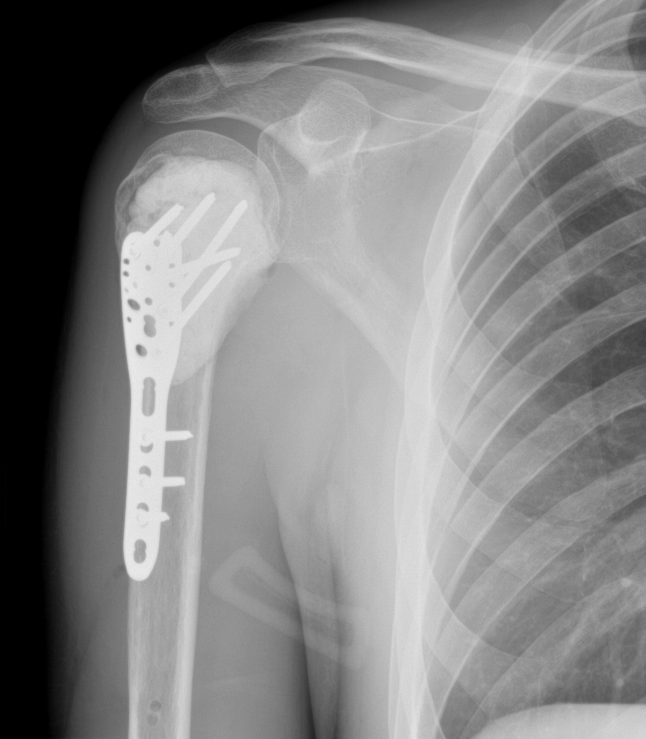

Post-operative X-ray showing plate and cement in the right proximal humerus

Post-op X-ray with plate and cement

In May 2022, I had limb salvage surgery: intralesional curettage with bone cement and a plate. That decision, to advocate for myself, to challenge the recommendation, to find a clinician who would work with me rather than just for me, that was the moment I became a researcher and an advocate. I just didn't know it yet.

Intralesional curettage with bone cement and plate at St Vincent's Private Hospital, Melbourne.